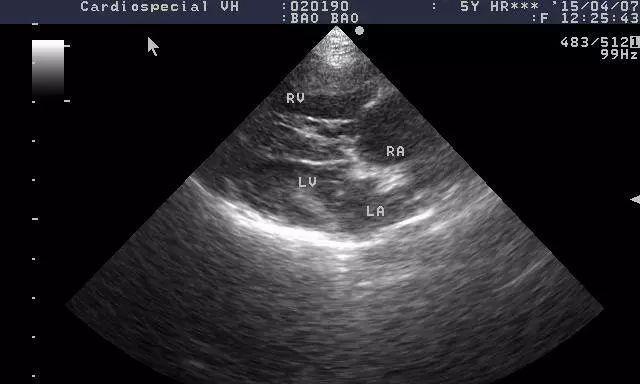

描述疾病在宿主体内的进展情况,包括心脏和肺动脉的破坏程度。

探讨以犬得心丝虫病的诊断方法和治疗手段,并强调早期发现和干预的重要性。